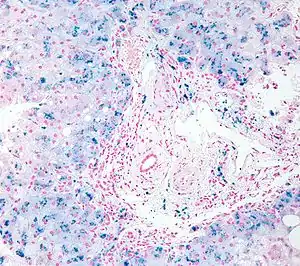

| Micrograph of liver biopsy showing iron deposits due to haemosiderosis. Iron stain. | |

Biopsy

Liver biopsy is the removal of small sample in order to be studied and can determine the cause of inflammation or cirrhosis. In someone with negative HFE gene testing, elevated iron status for no other obvious reason, and family history of liver disease, additional evaluation of liver iron concentration is indicated. In this case, diagnosis of hemochromatosis is based on biochemical analysis and histologic examination of a liver biopsy. Assessment of the hepatic iron index (HII) is considered the "gold standard" for diagnosis of hemochromatosis.